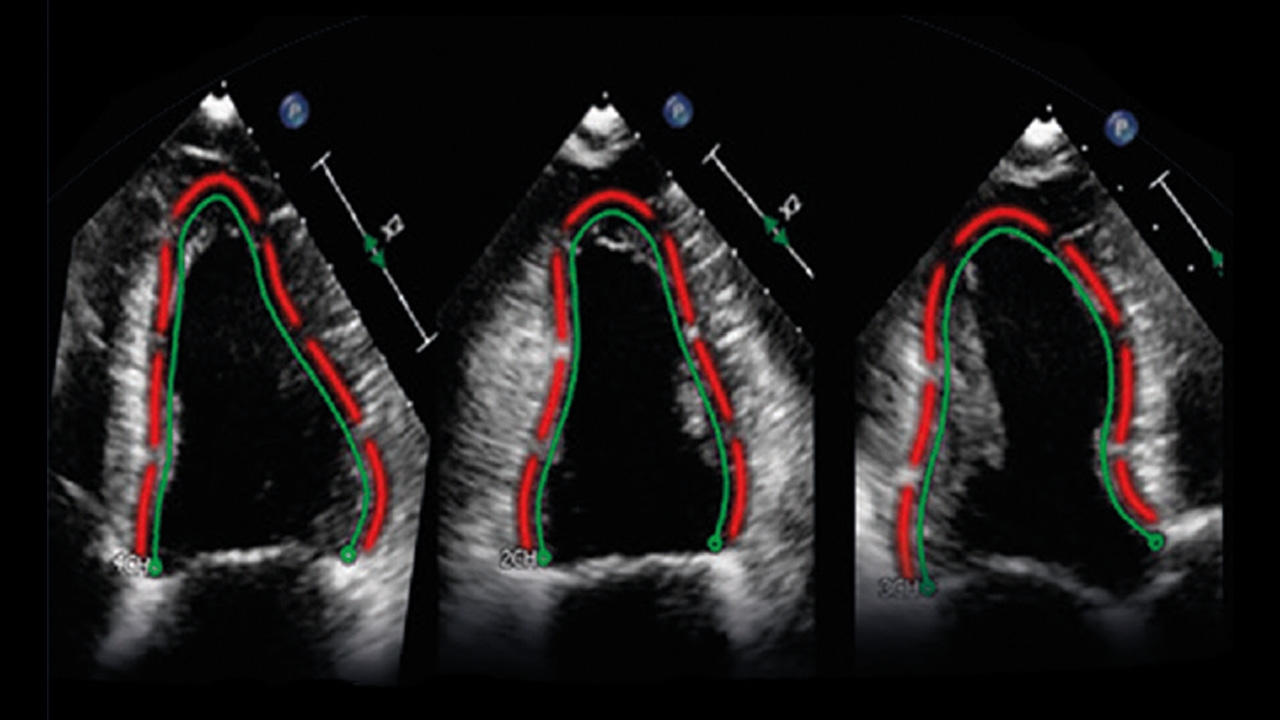

Philips a acquis TomTec Imaging Systems, un spécialiste allemand des logiciels d’analyse de l’image, pour un montant non dévoilé. L’apport de TomTec permettra d’affiner les analyses réalisées par ultrasons en cardiologie, obstétrique et gynécologie.